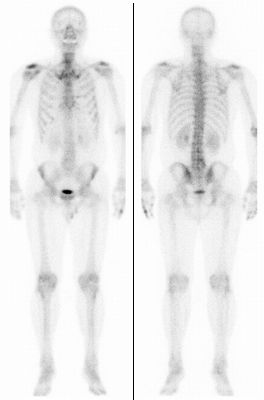

確定診断までの流れ がんの治療法 詳しく知りたい 前立腺がん

確定診断までの流れ がんの治療法 詳しく知りたい 前立腺がん